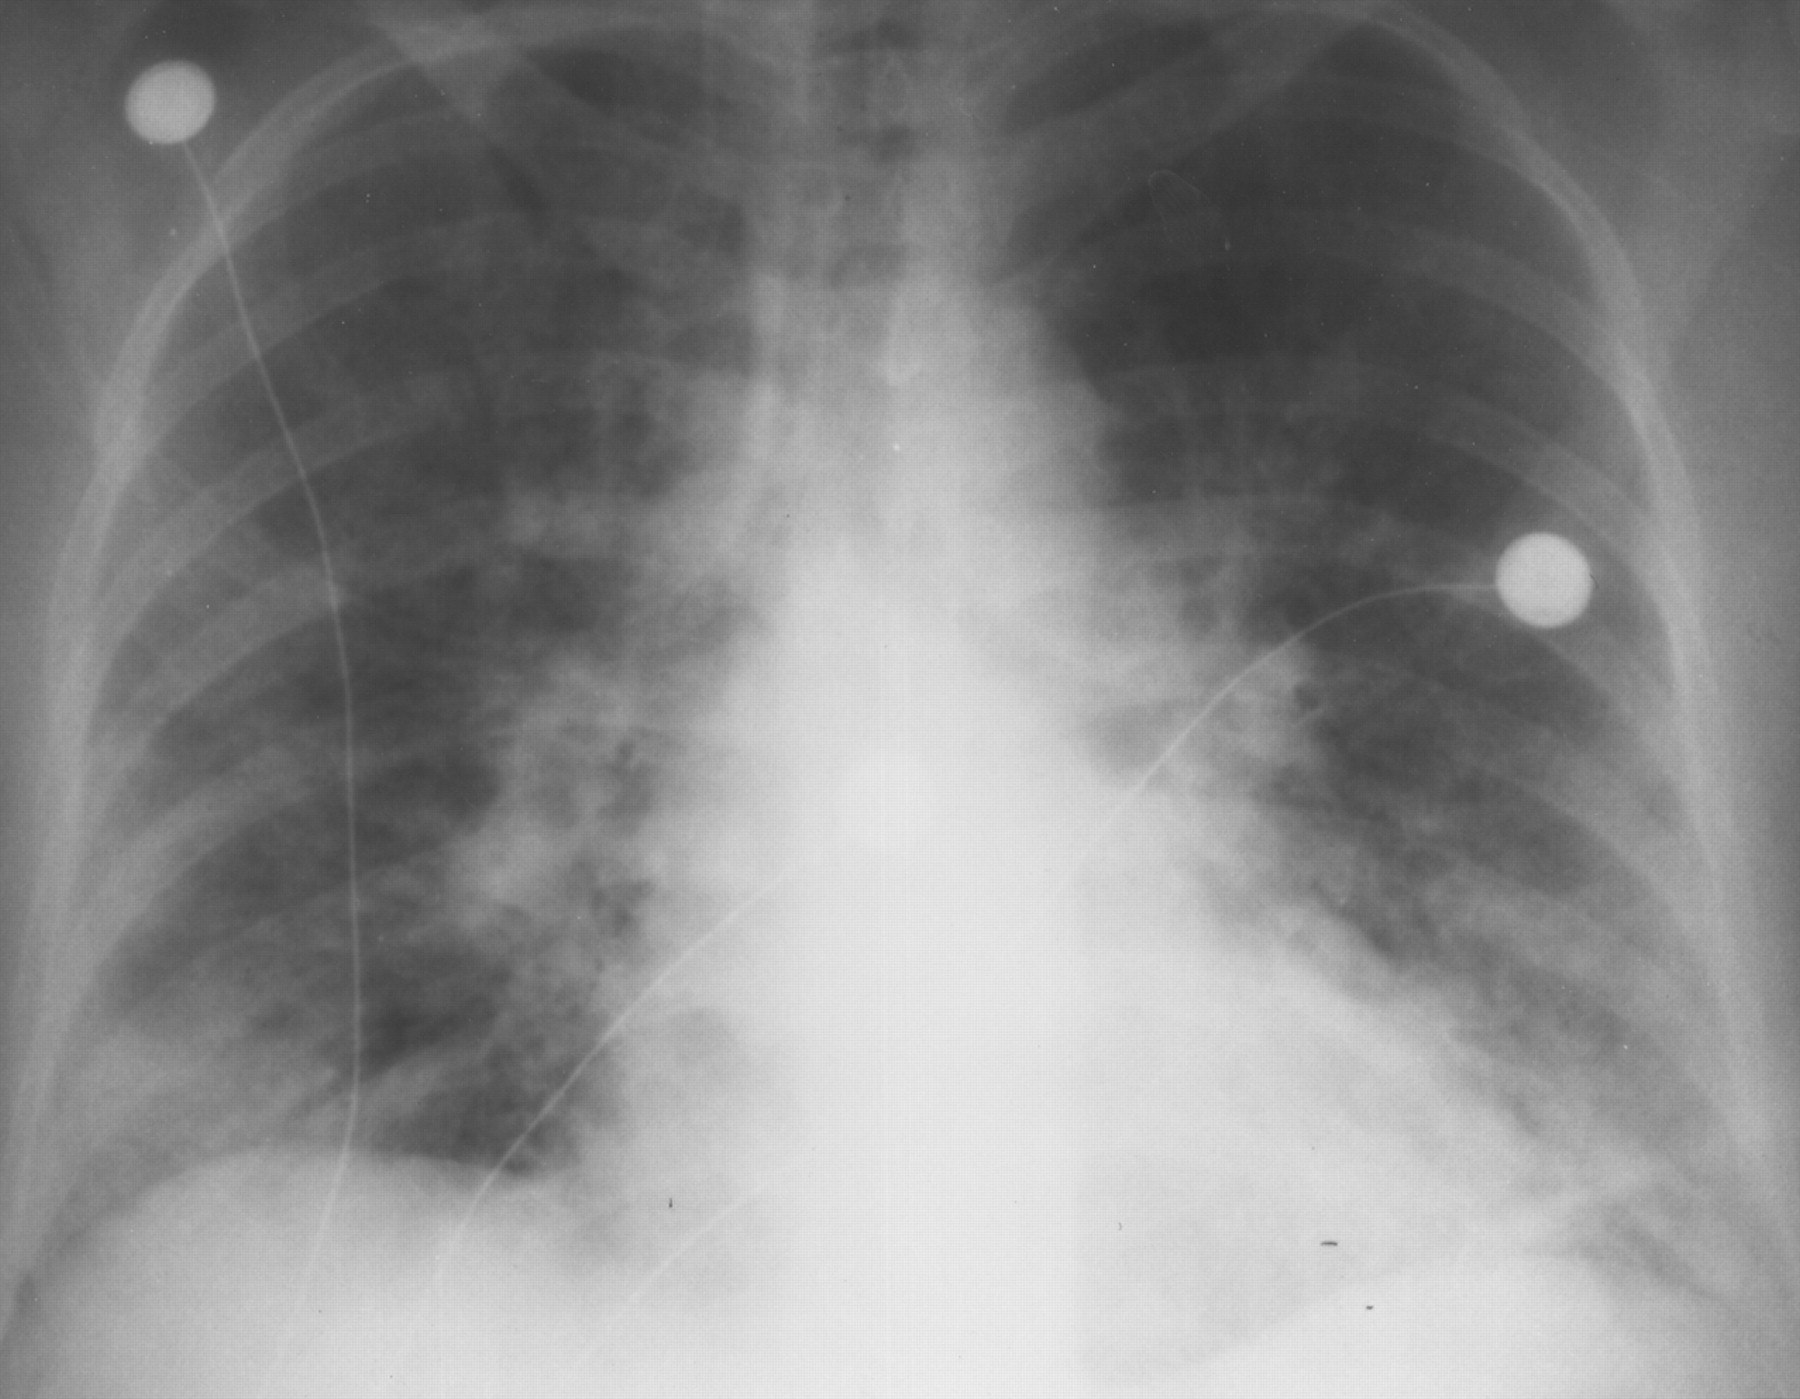

| Kerusakan jaringan paru. |

| Infeksi atau kerusakan tulang, sumsum tulang belakang, otak, kelenjar getah bening. |